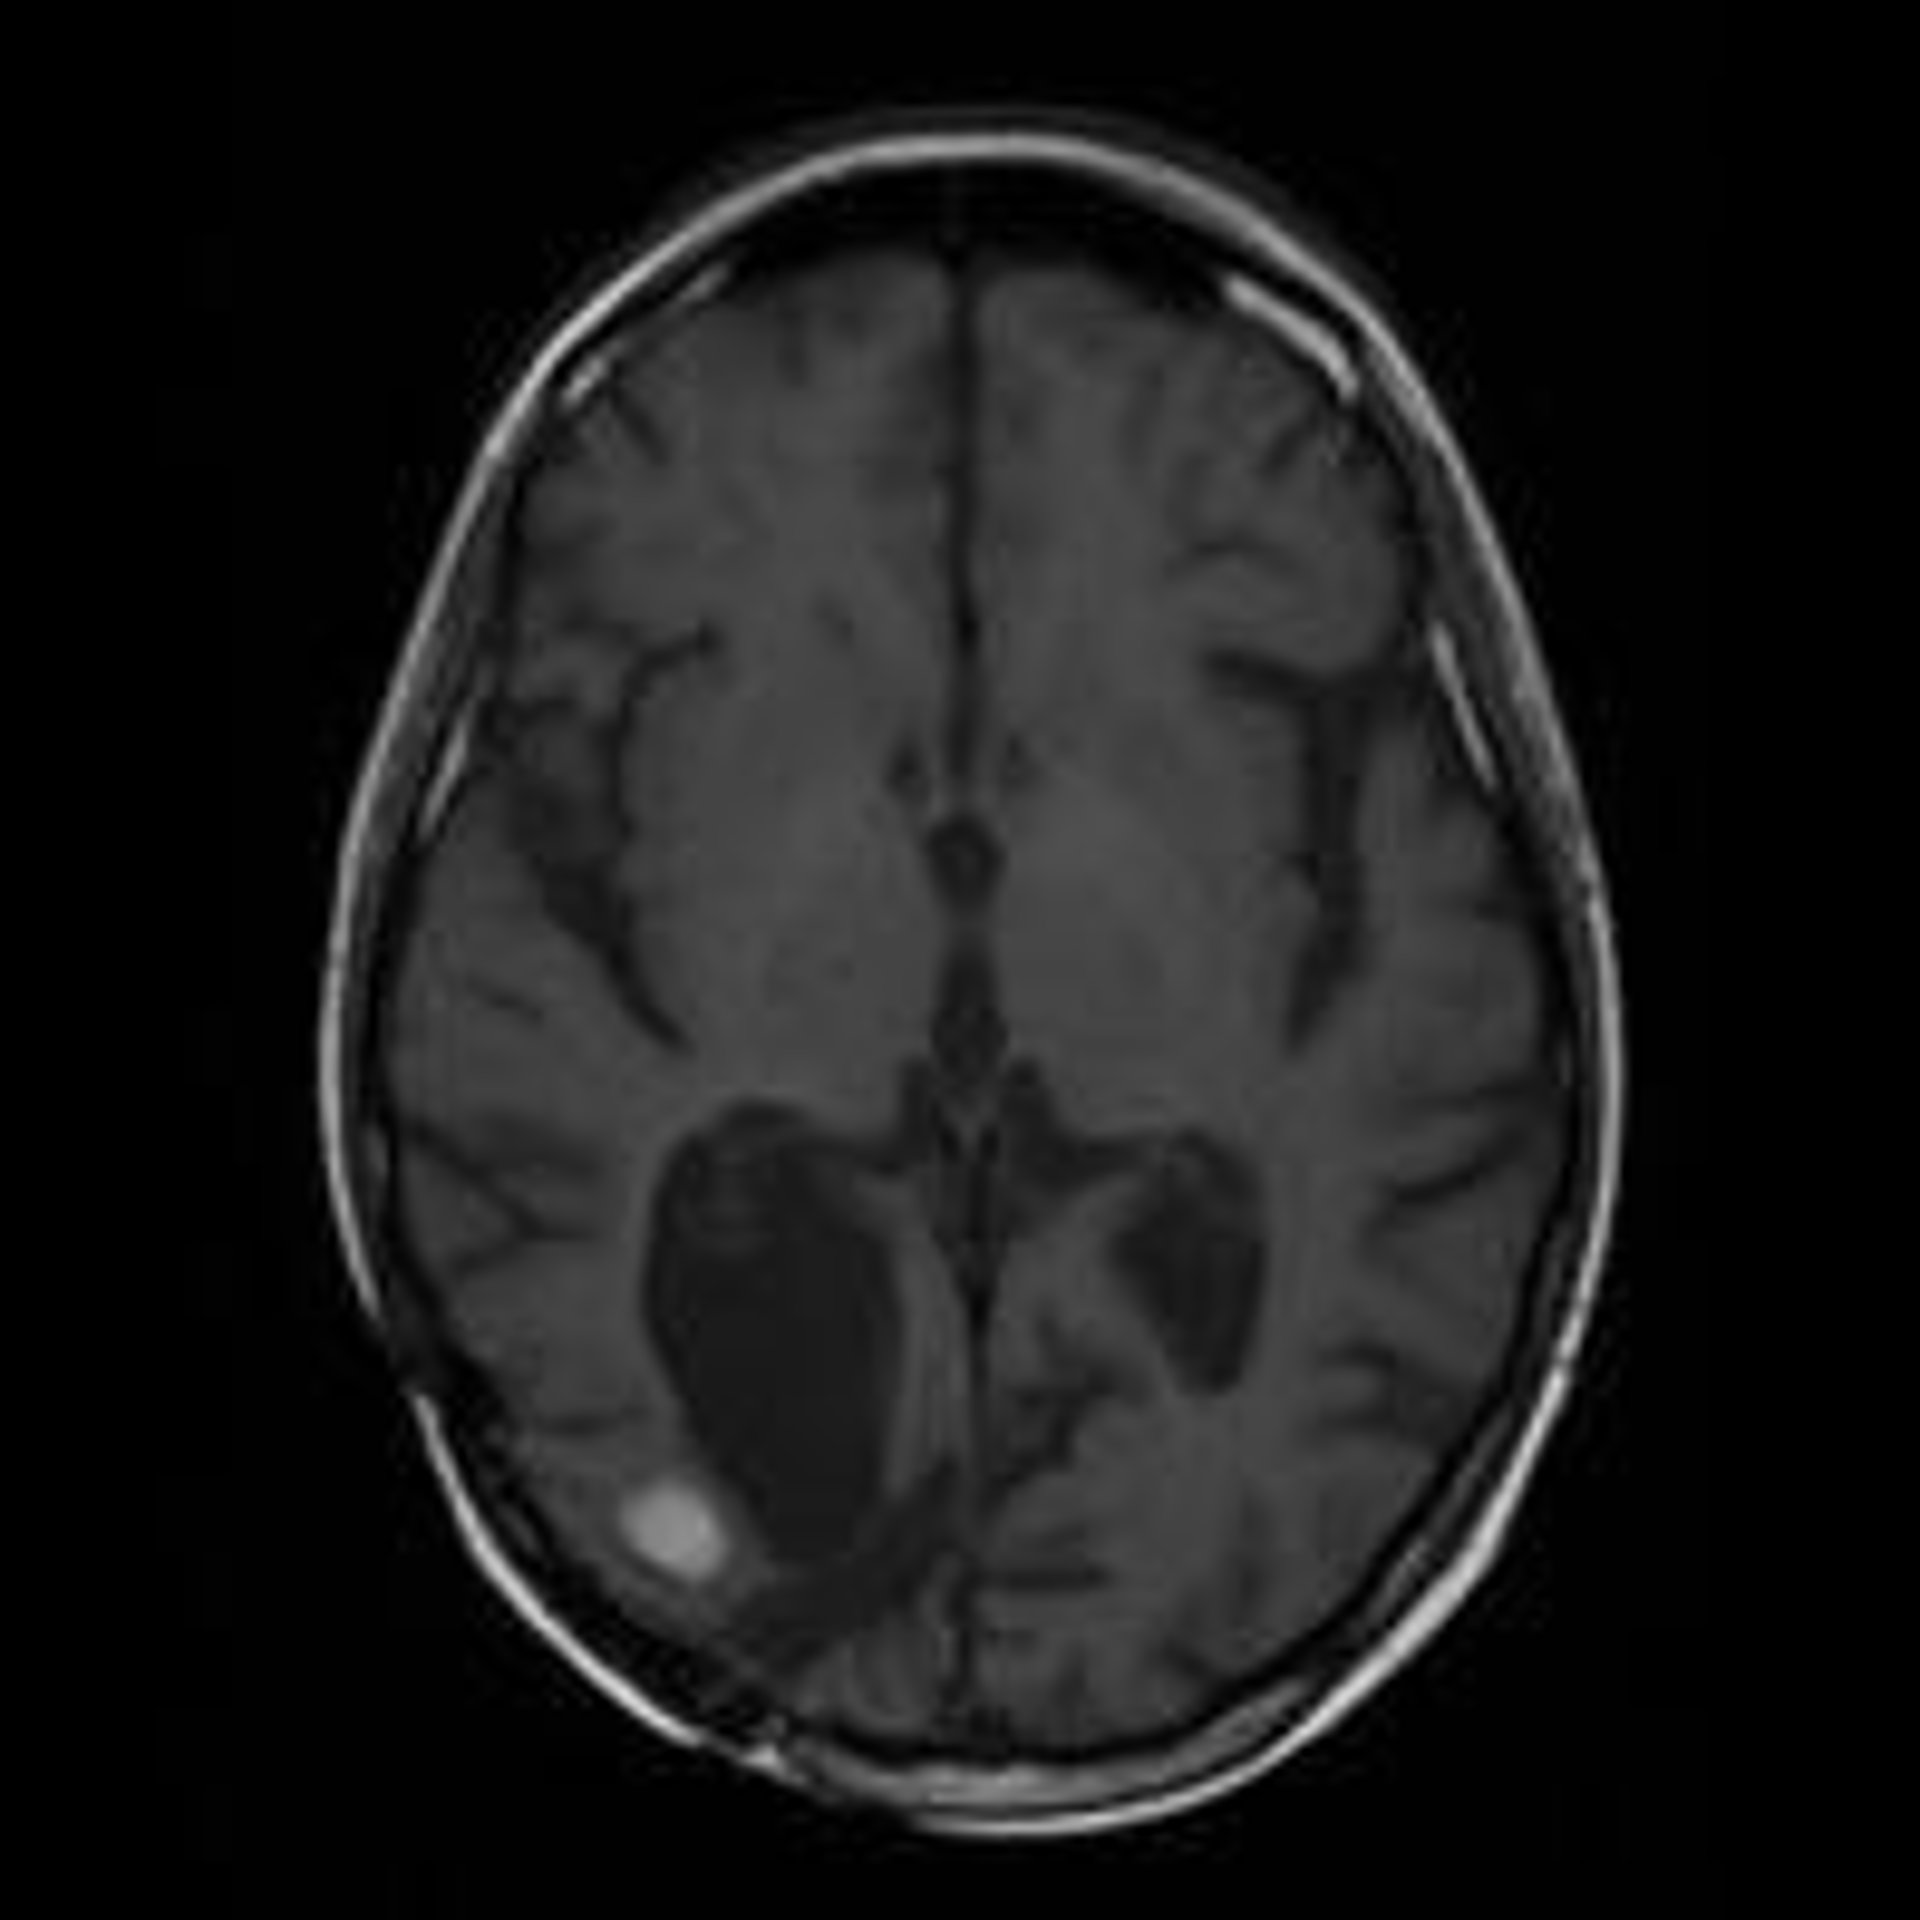

Resonancia Magnética De Un Cerebro Con Metástasis

Investigadores del Hospital del Mar de Barcelona han hallado un nuevo marcador genético vinculado a las hemorragias cerebrales, el gen Apoe E2, cuya presencia podría indicar una mayor probabilidad de sufrir hemorragias más importantes y por tanto un mayor riesgo de muerte o incapacidad.

Los resultados, que publica la revista 'Lancet Neurology', se han obtenido tras analizar la extensión de la hemorragia cerebral y su localización en 846 pacientes afectados por una hemorragia en la corteza cerebral y en 1.176 afectados por hemorragias en zonas cerebrales más profundas, todos ellos mayores de 55 años.

Los científicos han demostrado cómo, las personas portadoras de este gen, tienen unos vasos sanguíneos en el cerebro más vulnerables, por lo que en caso de que se produzca una hemorragia en la cercanía de estos vasos, éstos pueden romperse con más facilidad.